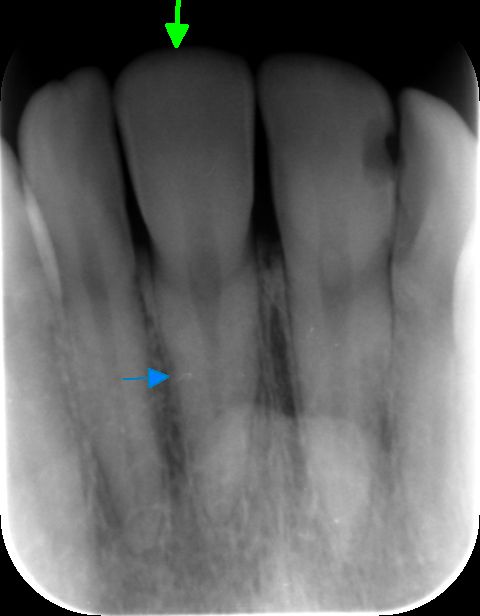

De tand is aangeduid met de groene pijl. Het betreft een voortand in de bovenkaak.

Moet ik mij zorgen maken? Ik vraag me ook af wat het felwitte lijntje (aangeduid met blauwe pijl) op de wortel is?